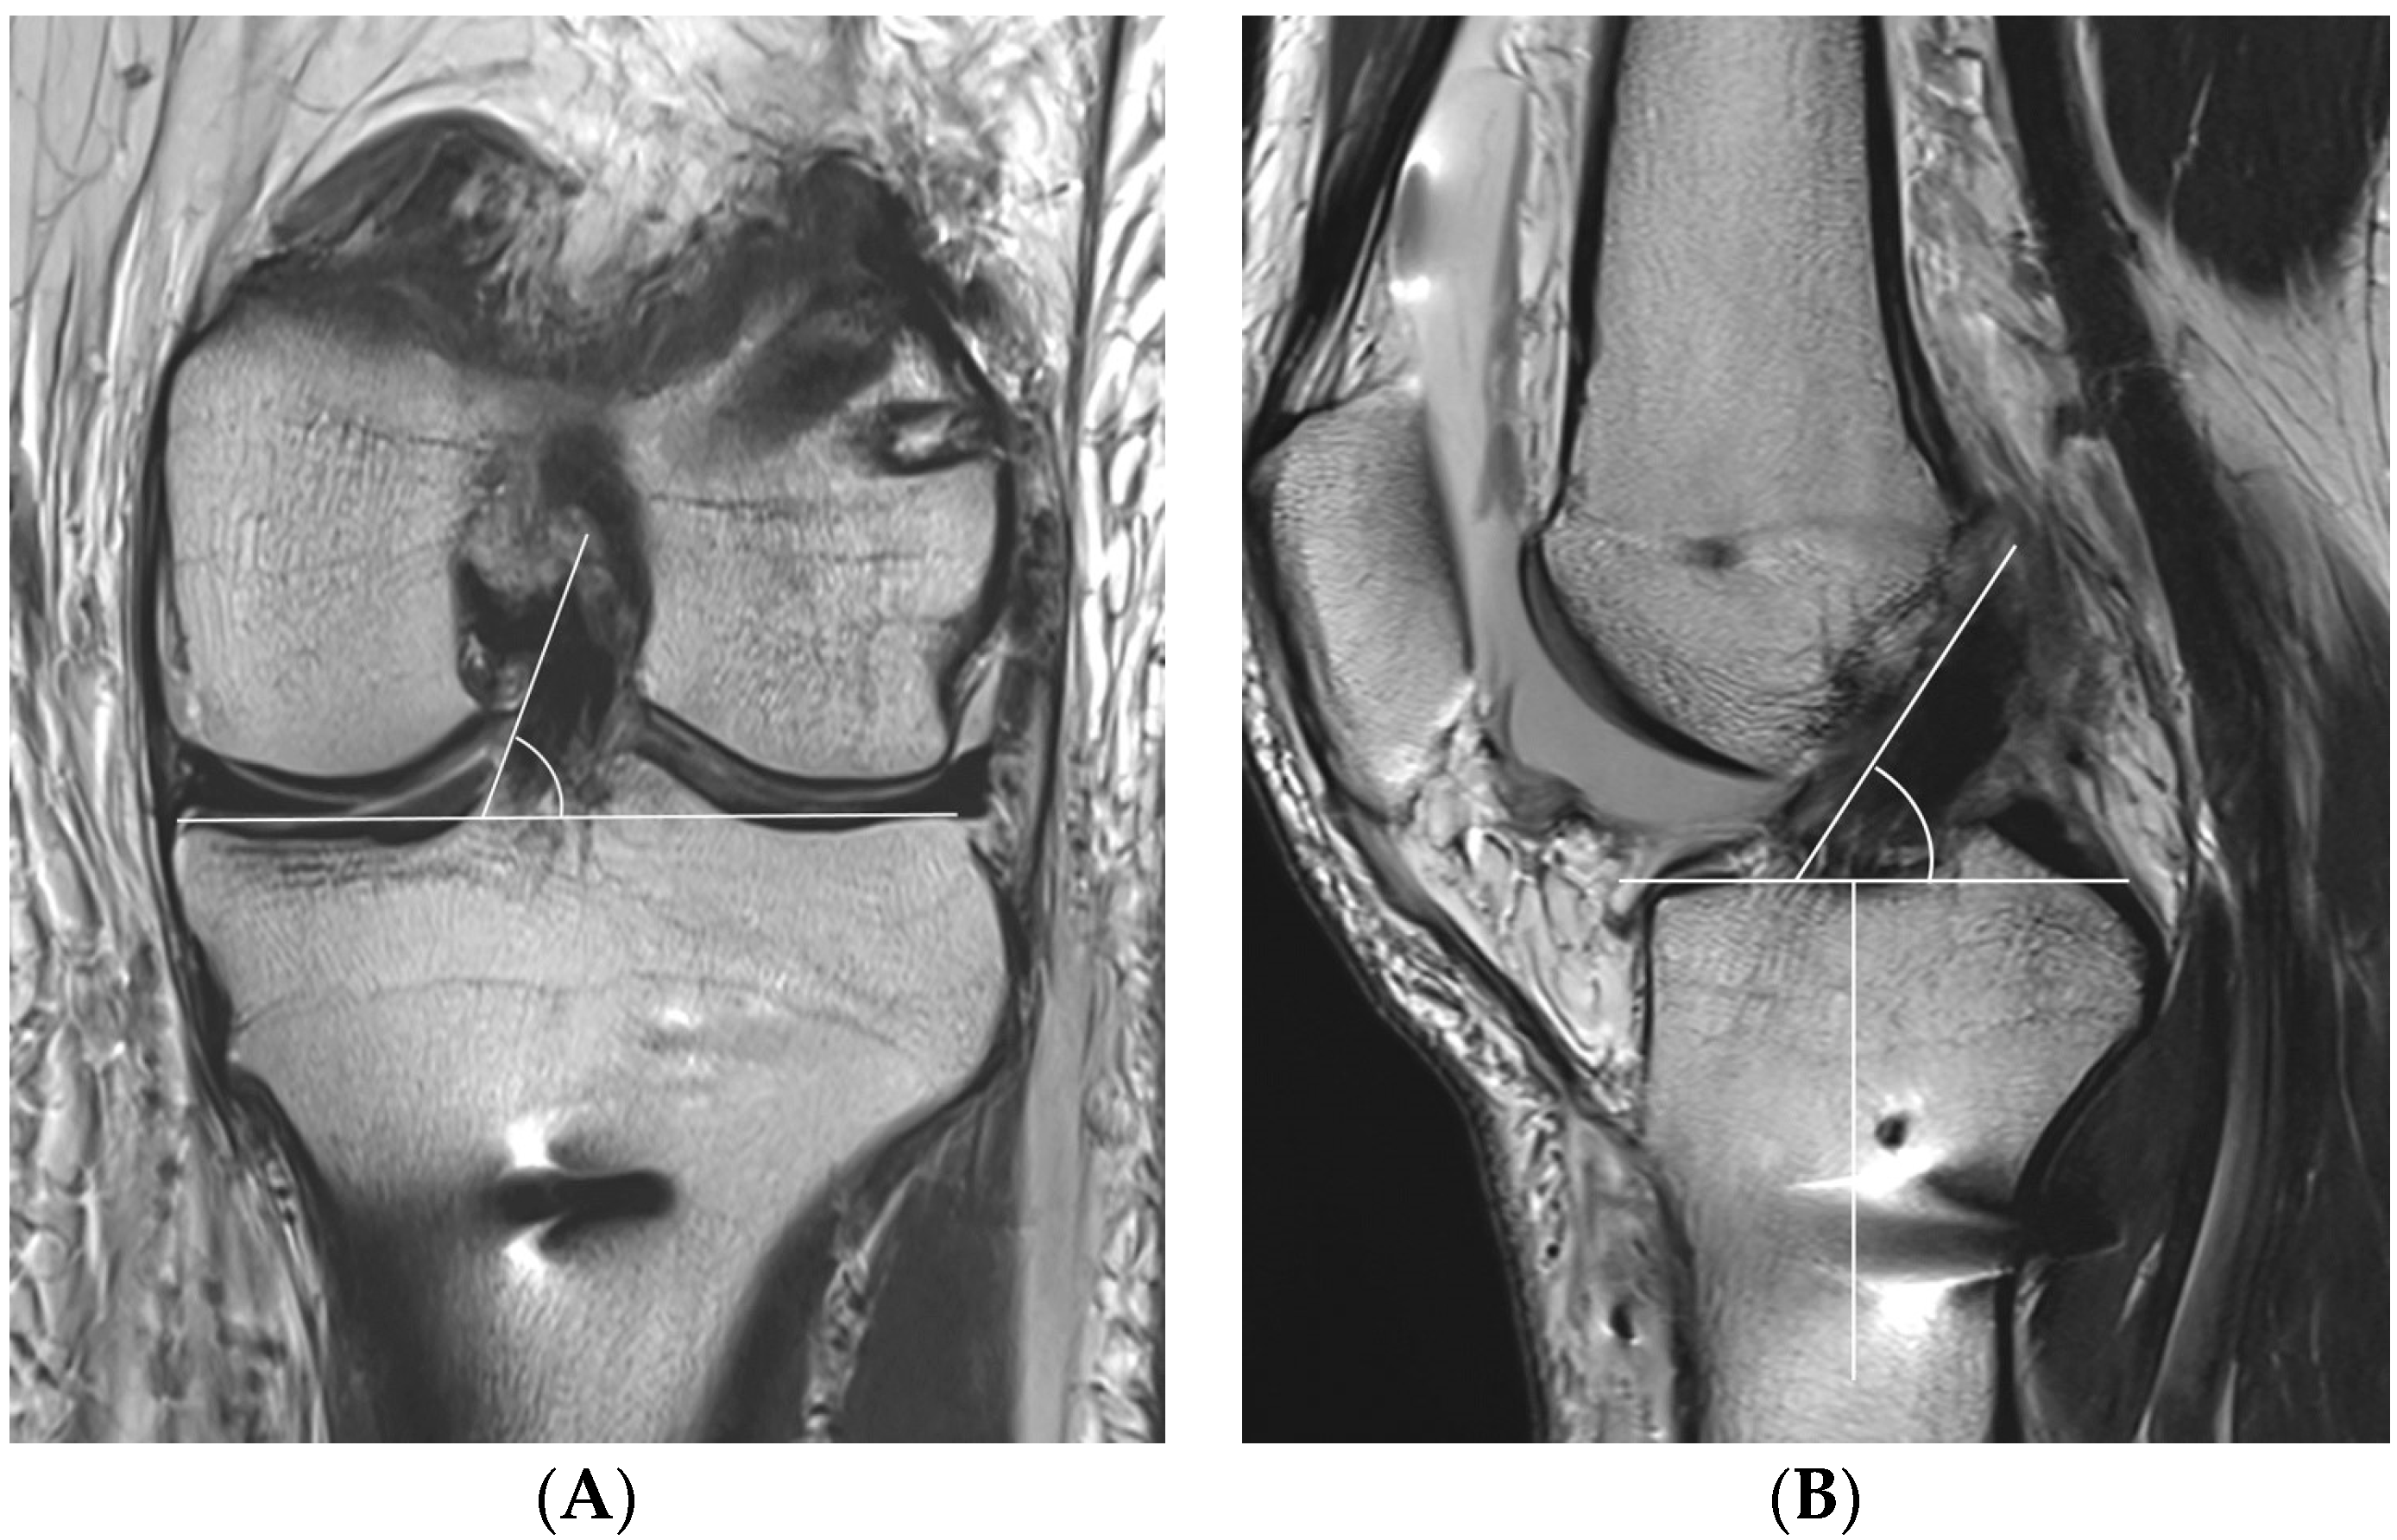

2.4. MRI Evaluation

One day after ACLR, all patients underwent MRI with a 3.0-T system apparatus (Signa HD, GE Healthcare; Milwaukee, WI, USA) to evaluate for graft inclination. The graft inclination on the coronal plane was defined as the angle between the medial margin of the ACL graft through more than one slice and a line parallel to the tibial plateau at the level of the middle of the medial collateral ligament (Figure 5A). Because the entire ACL graft is unable to be visualized on one slice, if the medial margin of the ACL graft is marked and scrolled while watching the monitor, a line can be clearly drawn. The graft inclination on the sagittal plane was defined as the angle between the anterior margin of the ACL graft and a line perpendicular to the long axis of the tibia at the level of the Blumensaat line (Figure 5B).

Figure 5. The coronal graft inclination (A) is defined as the angle between the medial margin of the anterior cruciate ligament (ACL) graft and a line parallel to the tibial plateau at the level of the middle of the medial collateral ligament. The sagittal graft inclination (B) is defined as the angle between the anterior margin of the ACL graft and a line perpendicular to the long axis of the tibia at the level of the Blumensaat line.